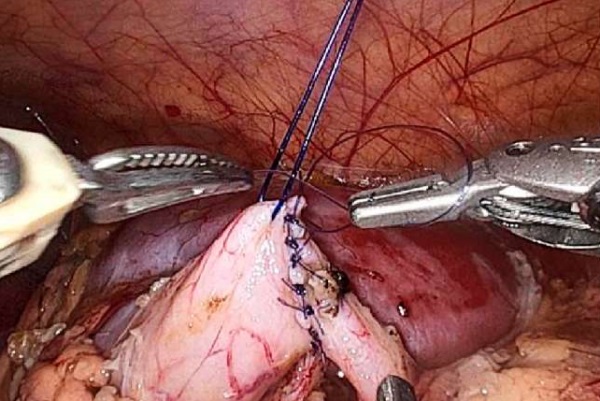

Введение. Обструкция пиелоуретерального сегмента (ОПУС) — самая частая причина хирургических вмешательств на верхних мочевых путях у детей. Нами проведён сравнительный анализ результатов применения робот-ассистированной лапароскопической пиелопластики (РАП) с использованием системы da Vinci Xi и традиционной лапароскопической пиелопластики (ЛП).

Заключение. Сравнительный анализ эффективности и безопасности использования РАП и ЛП при ОПУС у детей демонстрирует сопоставимые результаты по длительности хирургии и динамике регрессии дилатации чашечно-лоханочной системы в послеоперационном периоде. В качестве преимущества РАП по сравнению с ЛП следует считать сохранение физических кондиций оператора на всём протяжении формирования анастомоза, позволяющих формировать анастомоз максимально прецизионно, избегая компромисса между желаемым качеством наложения интракорпорального шва и реальным результатом на фоне неизбежной физической усталости оператора при использовании лапароскопического доступа.